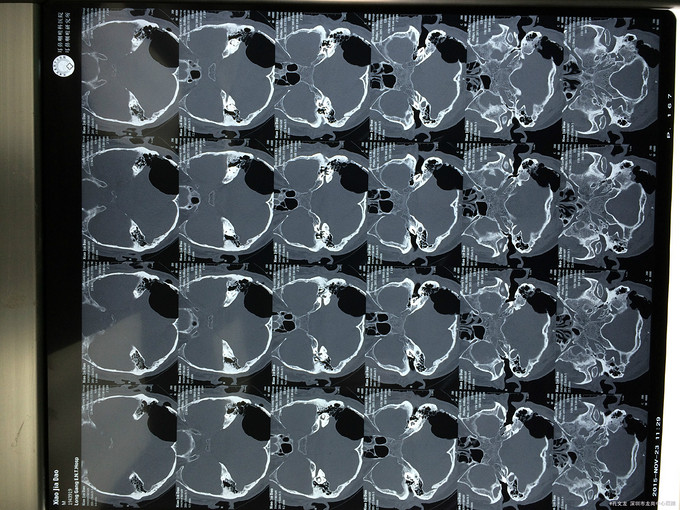

诊断:自发性颅内积气(张力性) 入院后予以完善相关检查,行颞骨乳突薄层CT扫面,考虑乳突气房内耳道漏气,粘膜瓣形成张力性气颅,再次开路手术创伤大,联合耳鼻喉科,行颅外手术,耳后入路磨除乳突气房,发现粘膜活瓣样活动,分辨漏气口,自取皮下筋膜,及带蒂肌皮瓣,填塞漏口及乳突气房,生物胶粘合,手术顺利,术后恢复良好。